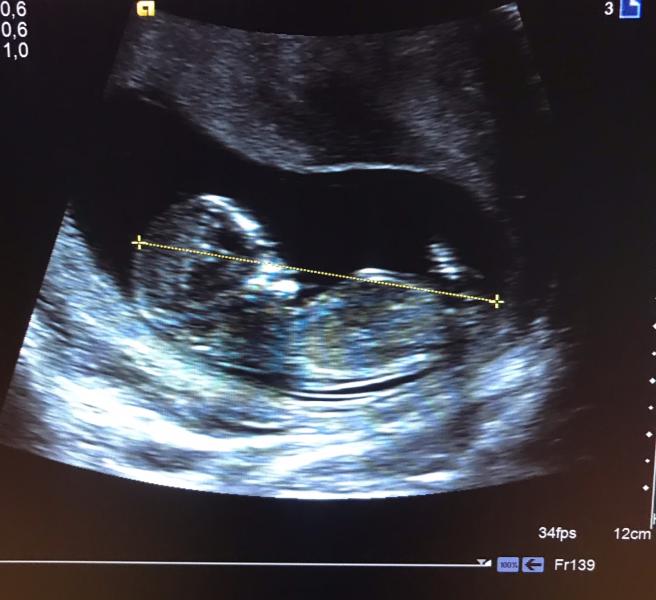

04.03.19. Это было так волнительно. Первый скрининг и встреча с настоящим человечком живущим внутри тебя. С будущей доченькой или сыночком.Без слез не обошлось ,особенно когда мне показали маленькую ручку с пальчиками .В этот момент я почувствовала самое настоящие счастье, счастье быть будущей мамой.

Первый скрининг😍 не знаю может ли быть что-то прекраснее) я плакала на каждом узи😂 на первом была в 6 недель, услышала сердцебиение- пустила слезу (до этого была ЗБ), потом в 9 недель- уже увидела человека)) пустила слезу, как же быстро он растёт. Потом 12 недель- первый скрининг, уже большой человек)) растрогали тоже пальчики)) потом в 19 недель- второй скрининг и мысль «капец! И это во мне?!?» сказали окончательно пол, показали личико- всплакнули с мужем вдвоём от 3д узи😂😂😂 что будет на третьем не знаю)))